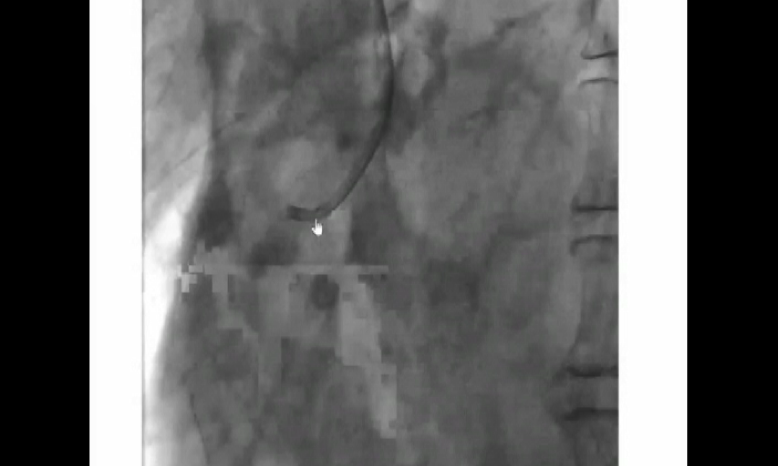

Power Positionとは

IKARI Left カテーテルのバックアップ力を増すためのシンプルで有効な方法がPower positionで、アンカーバルーンテクニックと同等のバックアップが得られます。

⇒ 回さず、押すだけ」

Power positionでは、対側大動脈に当たる角度が90度になり、強いバックアップ力を生み出します。左冠動脈のPower positionでは、IKARI Left カテーテルは深く入らないため、LMTの損傷を起こさず安全に使用できます。